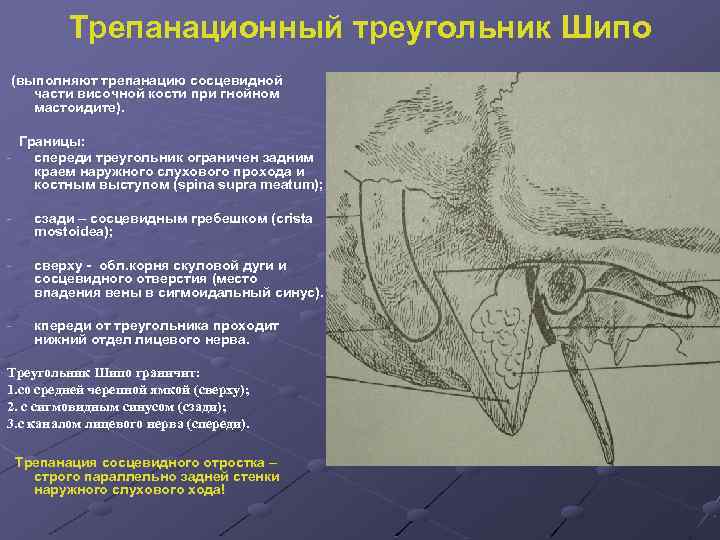

Анатомия сосцевидного отростка